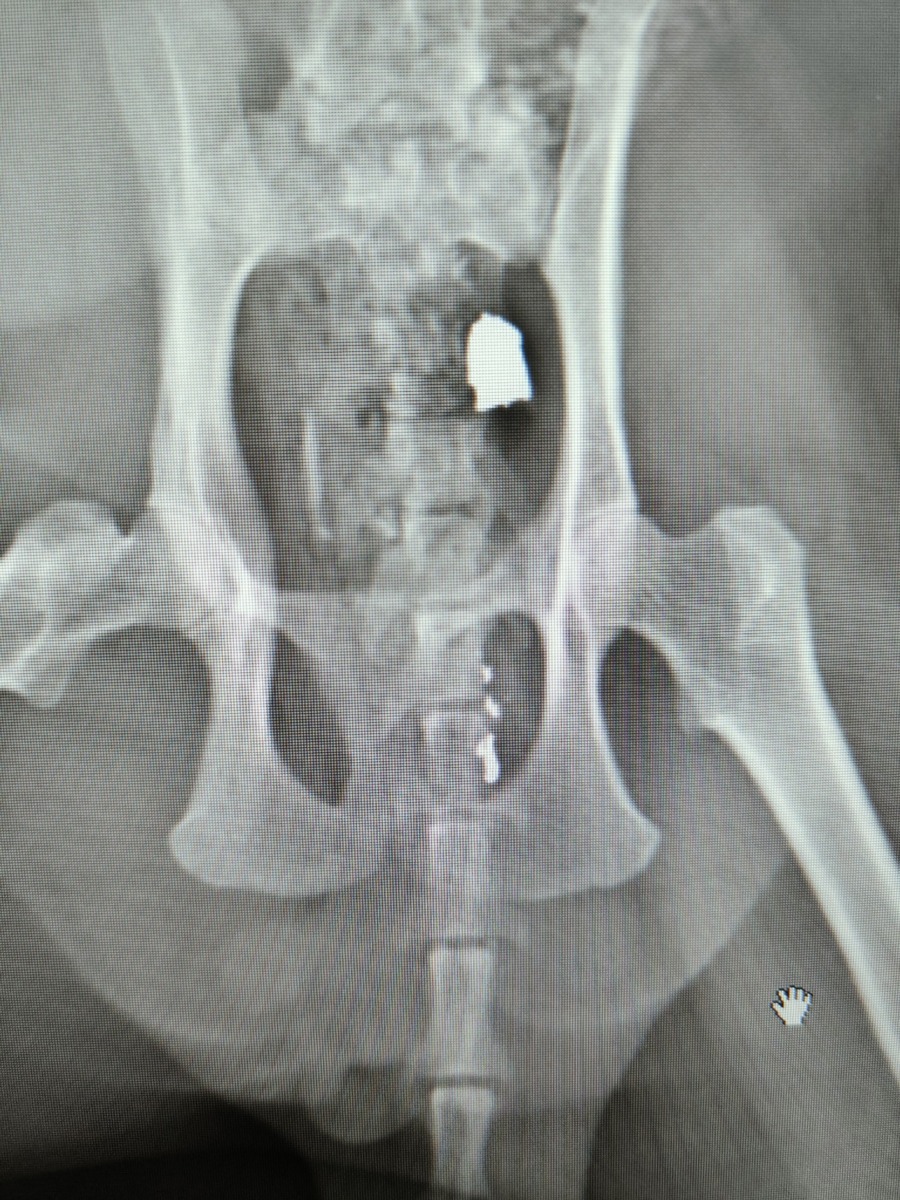

Как рассказала редакции SmolNarod Виктория, пуля была обнаружена в теле животного случайно, в ходе планового осмотра перед кастрацией. Прежде чем попасть к нынешней хозяйке, кот жил на улице, поэтому определить, когда и тем более кто совершил выстрел, не представляется возможным. Благо, снаряд застрял под кожей хвостатой жертвы, не причинив значительных повреждений.

«Спасать его не пришлось, пуля просто находилась под кожей и не причиняла коту дискомфорта на момент приема. Рана после выстрела зажила самостоятельно и наружных травм обнаружено не было. Мы извлекли пулю планово одновременно с проведением кастрации», — поделилась ветеринарный врач.